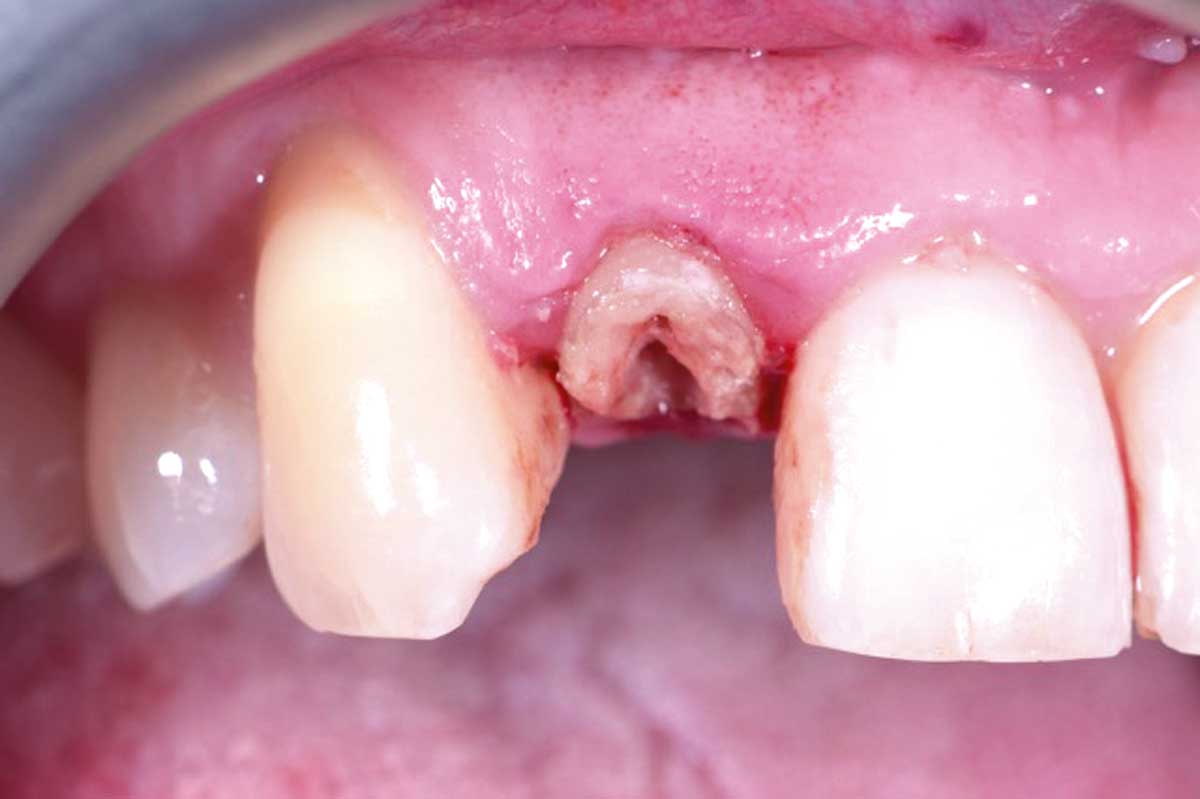

03/13 - Root condition, gingival zenith higher than the 11, intact distal papilla and some recession in mesial papilla

Immediate implant placement in the maxilla with contour GBR - Dr. K. Loukas